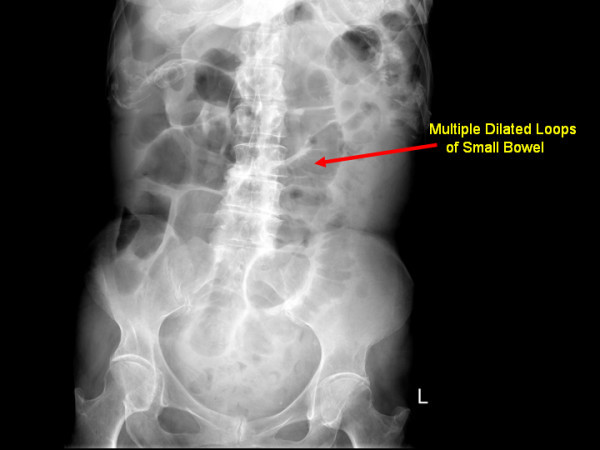

How does SBO present (4)? What’s most common cause?

Adhesions! (operations)

Complications of SBO (2)?

Management (2)

Strangulation vs. Perforation

Mgmt = [Surgical Exploration] vs. [NPO & IVF –> NG tube suction]